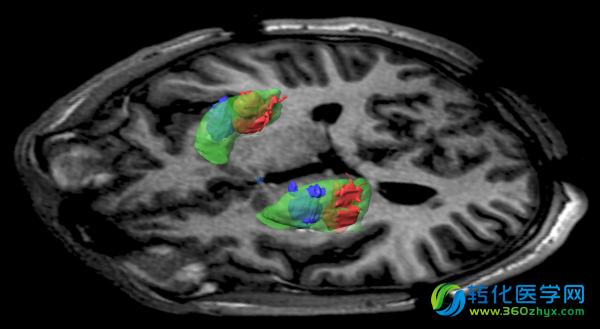

Voyager进行的一项新实验,旨在将更高层次的DNA输送到人脑内,来实现更好的结果。要做到这一点,Bankiewicz开发了一个系统,通过加压管注入含基因的病毒颗粒,而病人躺在核磁共振成像扫描仪内。那样的话,外科医生可以看到硬膜,该区域是DNA最终到达的部位,并确保充分治疗。针对帕金森病,还有其他的基因治疗方案正在计划或者已经进行。美国国立卫生研究院开展的一项试验,旨在增加一种生长因子和再生细胞。一家欧洲公司Oxford BioMedica正尝试多巴胺替代疗法来治疗帕金森病。

将ADDC使用化学标记,这样医生可以看到它在病人脑中发挥作用

尽管治疗工作没有按照计划进行,早期的研究表现出Voyager的方法相比其他方法的优势。将AADC使用化学标记,这样医生可以看到它在病人的大脑内部工作。事实上,几年后,在UCSF患者大脑内,仍然能看到不断产生合成多巴胺的酶。